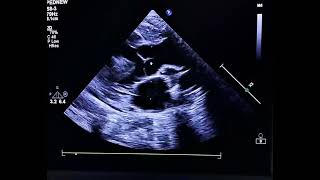

Parasternal Short axis - RWMA Assessment